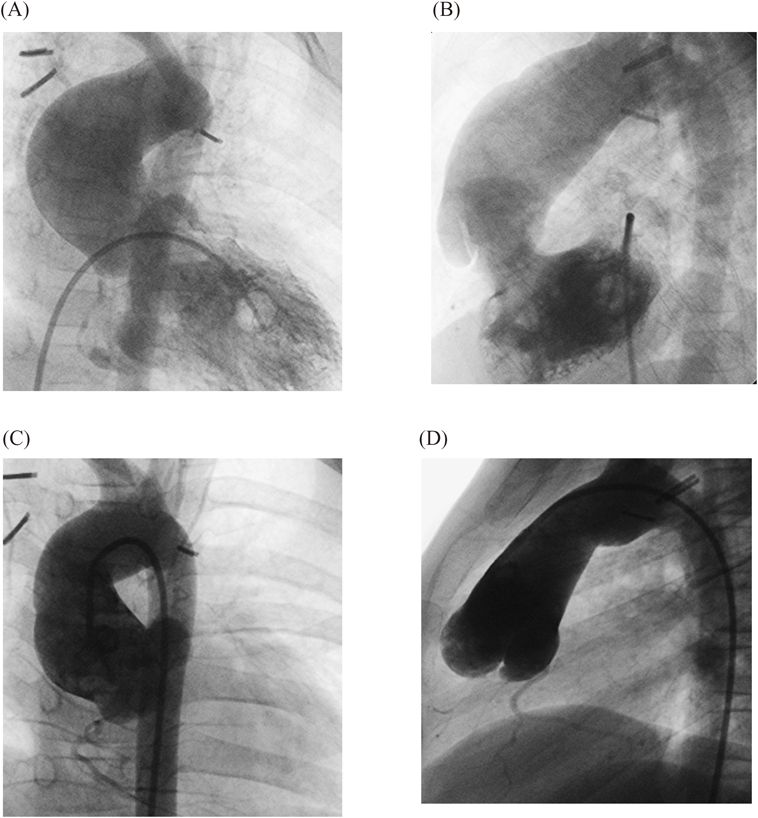

Images of pre- to postoperative changes of two typical cases are shown. Fig. 3 presents lateral view images of patient 1 obtained using aortic angiography preoperatively and 6 years postoperatively. The ascending aorta, which was dilated preoperatively, reduced in size postoperatively, and the retroaortic space enlarged and its size maintained.

Fig. 3 Anterior and lateral views of the ascending aorta in case 1

A, B) Preoperative angiogram. C, D) Postoperative angiogram 6 years postoperatively.